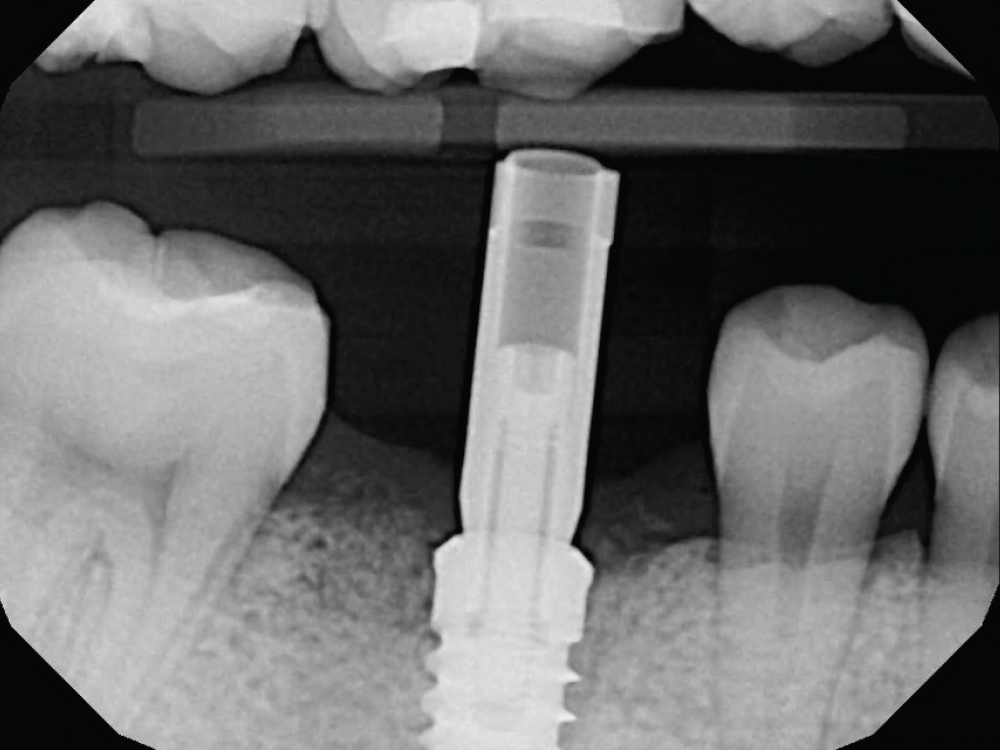

HAHN™ TAPERED IMPLANT SCAN BODY | INCLUSIVE® TITANIUM SCAN BODY

Engineered to enhance the precision of digital impressions, the new Hahn™ Tapered Implant Titanium Scan Body and the Inclusive® Titanium Scan Body, available for most major implant systems, are produced from medical-grade titanium, can be sterilized, and offer a durable alternative to traditional scanning abutments.

Suitable for use in both the anterior and posterior, the new scan bodies feature a microtextured surface that does not require powder or sprays, and their improved geometry enhances the accuracy of the image acquisition.

The new Hahn Titanium Scan Body is the latest addition to the extensive prosthetic options available for the Hahn Tapered Implant System. The Inclusive Titanium Scan Body — the latest addition to the Glidewell family of Inclusive Prosthetic Components — offers a high-quality alternative to original equipment manufacturer (OEM) components at a fraction of the price. The Inclusive Titanium Scan Body is currently available for ASTRA TECH Implant System®, BIOMET 3i™ Certain®, Hiossen® HG System, MegaGen AnyRidge®, Nobel Biocare NobelActive®, Nobel Biocare NobelReplace®, and Zimmer Dental Screw-Vent®. New scan bodies will soon be available for additional implant systems.